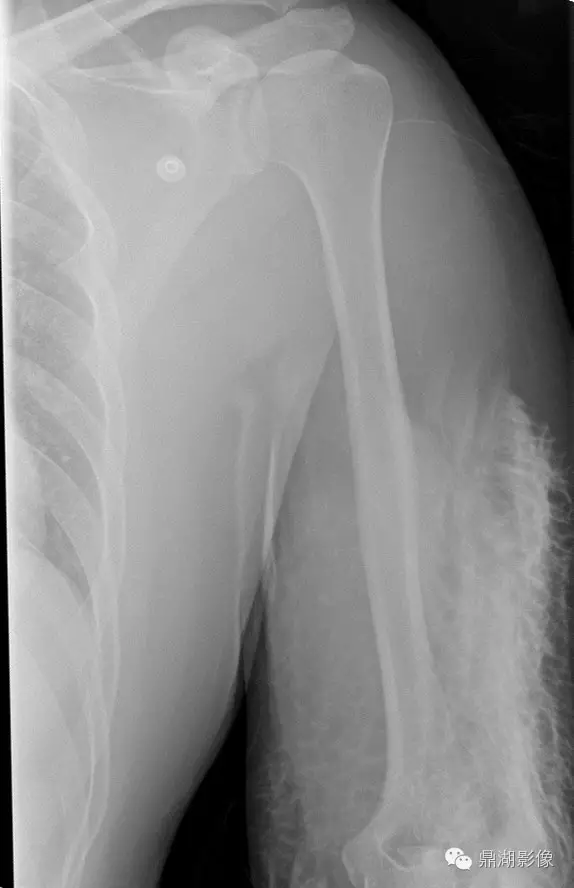

· 患者,男,35

· CT增强扫描后肘部疼痛

我想学影像的,不看片子都知道出问题了吧?但是看了片子才发现,这么严重。